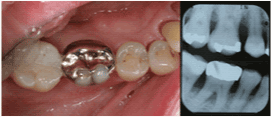

| Maxillary Right First

Molar |

4 |

89.2% |

|